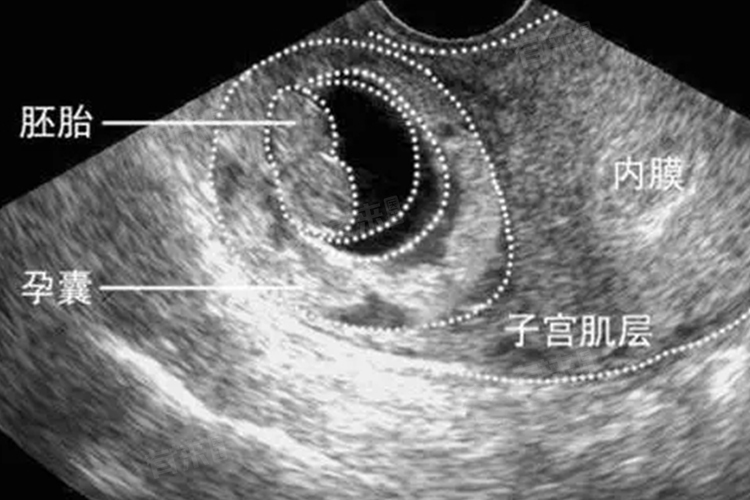

3、超声检查:这是最直接和准确的方法。通过超声检查可以直接观察子宫内是否还有孕囊以及残留物的情况。如果子宫内没有孕囊回声,且宫腔线清晰,通常表示孕囊已排出。